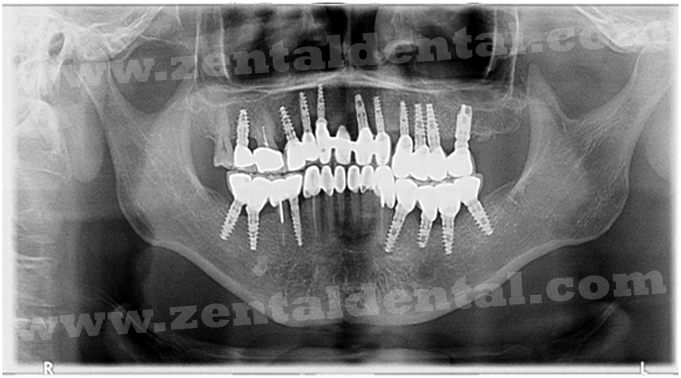

After Implant Insertion After Implant Insertion

After Six Months Implants With Super Structure (Abutments) After Six Months Implants With Super Structure (Abutments)